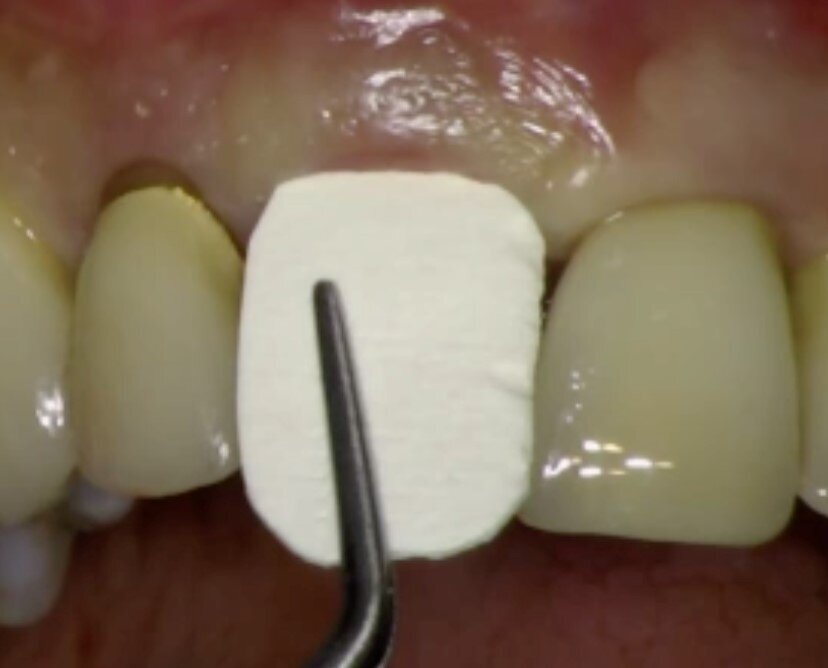

Nel caso in questione si pensò di utilizzare questa tecnica per favorire la possibilità alla paziente di avere un provvisorio immediato evitando di dovere intervenire con protesi mobili oppure andando a compromettere gli elementi adiacenti ancora ben funzionanti. La paziente venne pre-medicata con Ambramicina 250 mg (4 al dì) a partire da due giorni prima dell’intervento. Dopo aver somministrato l’anestesia locale con tecnica P-ASA6 utilizzando la Wand (Milestone) con articaina 1.200.000 l’elemento 21 veniva rimosso con molta cautela (Fig. 8). Il tessuto di granulazione presente all’apice rimosso con curettes, e l’alveolo post estrattivo disinfettato con H2O2 e Clorexidina 0.12%. La preparazione dell’intervento con conseguente carico immediato prevedeva l’uso di una mascherina chirurgica utile sia al posizionamento dell’impianto che alla successiva cementazione della corona provvisoria sull’impianto (Fig. 9). Il sito veniva preparato con le frese del caso ed era inserito un impianto Diagram (Schütz Dental) in posizione palatale (Fig. 10). Una volta inserita la fixture alla profondità e posizione corretta, con i bisturi da tunnelizazione veniva creato lo spazio vestibolarmente (laddove la frattura aveva completamente riassorbito la corticale) per l’inserzione di una lamina corticale ossea flessibile (Flex cortical sheet, Bioteck) dello spessore di 0.5 mm. La lamina veniva prima ritagliata (Fig. 11) poi idratata con soluzione fisiologica sterile per circa 30 secondi, ed infine inserita in posizione (Fig. 12).

A questo punto veniva avvitato sull’impianto un moncone provvisorio, completato l’innesto di materiale biocompatibile con osso equino collagenato (OX granules, Bioteck) nel gap esistente tra la fixture e la lamina, poi veniva connessa al moncone provvisorio la corona provvisoria in resina (Fig. 13). La rx di controllo post intervento evidenzia la buona riuscita della procedura e la corretta connessione tra moncone e fixture (Fig. 14). Sei mesi più tardi alla rivalutazione e rimozione della corona provvisoria (Fig. 15) si può ben notare come questa procedura abbia permesso di mantenere integri i tessuti peri-implantari, di aver favorito la creazione di un tunnel mucoso spesso e maturo. I tessuti con e senza la corona provvisoria mostrano un aspetto naturale e le caratteristiche di una gengiva in salute (Figg. 16a, 16b).